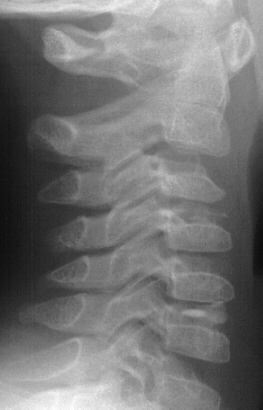

most common outcome of this process is auto fusion of the calcified disc

spaces over approximately 3 months period of time.

This

condition can cause disc protrusion severe enough to cause spinal cord

symptoms.

The

anatomic location of this calcification is in the nucleus pulposus.

Disc

calcification in children is more common in boys.